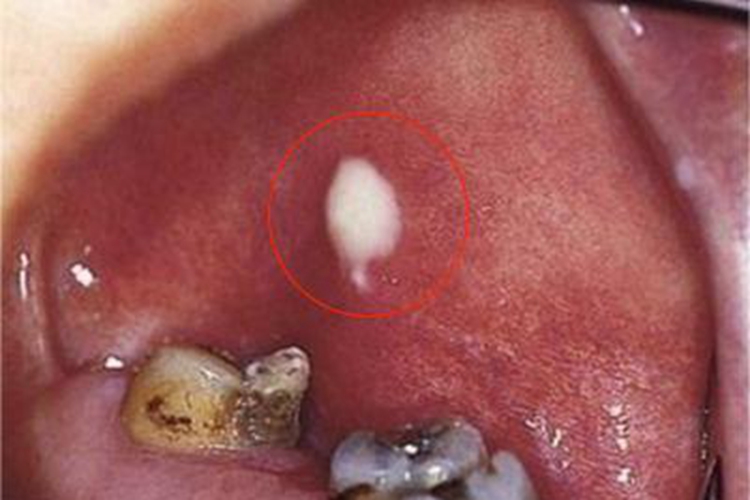

腮腺导管口明显红肿、疼痛,口腔内化脓,局部黏膜红肿,轻轻按摩腺体,可见脓液自导管口溢出。全身中毒症状明显,可有高热,脉搏、呼吸增快等。